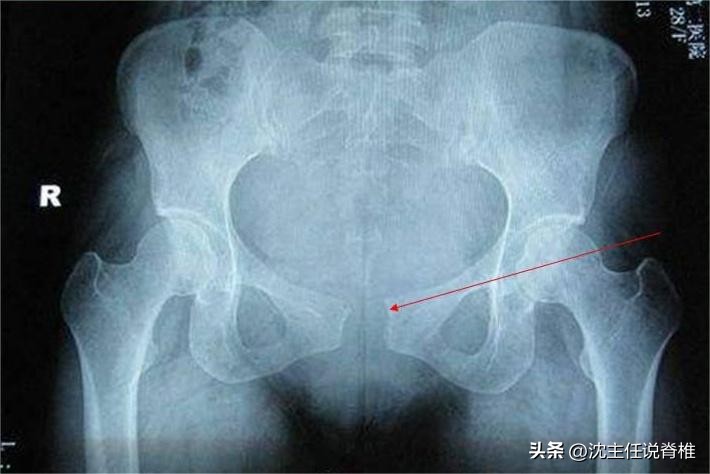

耻骨是位于骨盆前方的两块骨头,两者之间靠韧带及纤维软骨组织连接,形成耻骨联合。

正常情况下,耻骨联合间隙为 4~6mm 。但由于女性妊娠期间身体会分泌较多的松弛素,导致骨盆较孕前 不稳定 。

随着胎儿在子宫内慢慢长大及生产中出现的各种状况,耻骨联合在异常受力时,发生断裂且间隙 超过10mm 即为 “耻骨联合分离” 。